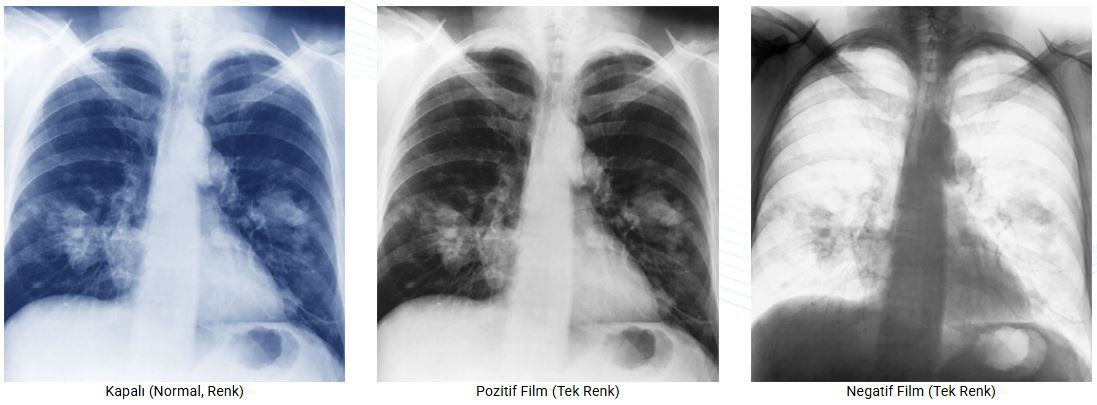

- DICOM Bölüm 14 GSDF standardı ile uyumlu

- Ortam ışığı değişimi için DICOM ön ayarı ve DICOM eğrisini otomatik düzeltme

- DICOM Bölüm 14 GSDF

- 10-bit Renk Derinliği

- DICOM Bölüm 14 GSDF standardı ile uyumlu

- Ortam ışığı değişimi için DICOM ön ayarı ve DICOM eğrisini otomatik düzeltme

- DICOM Bölüm 14 GSDF

- 10-bit Renk Derinliği